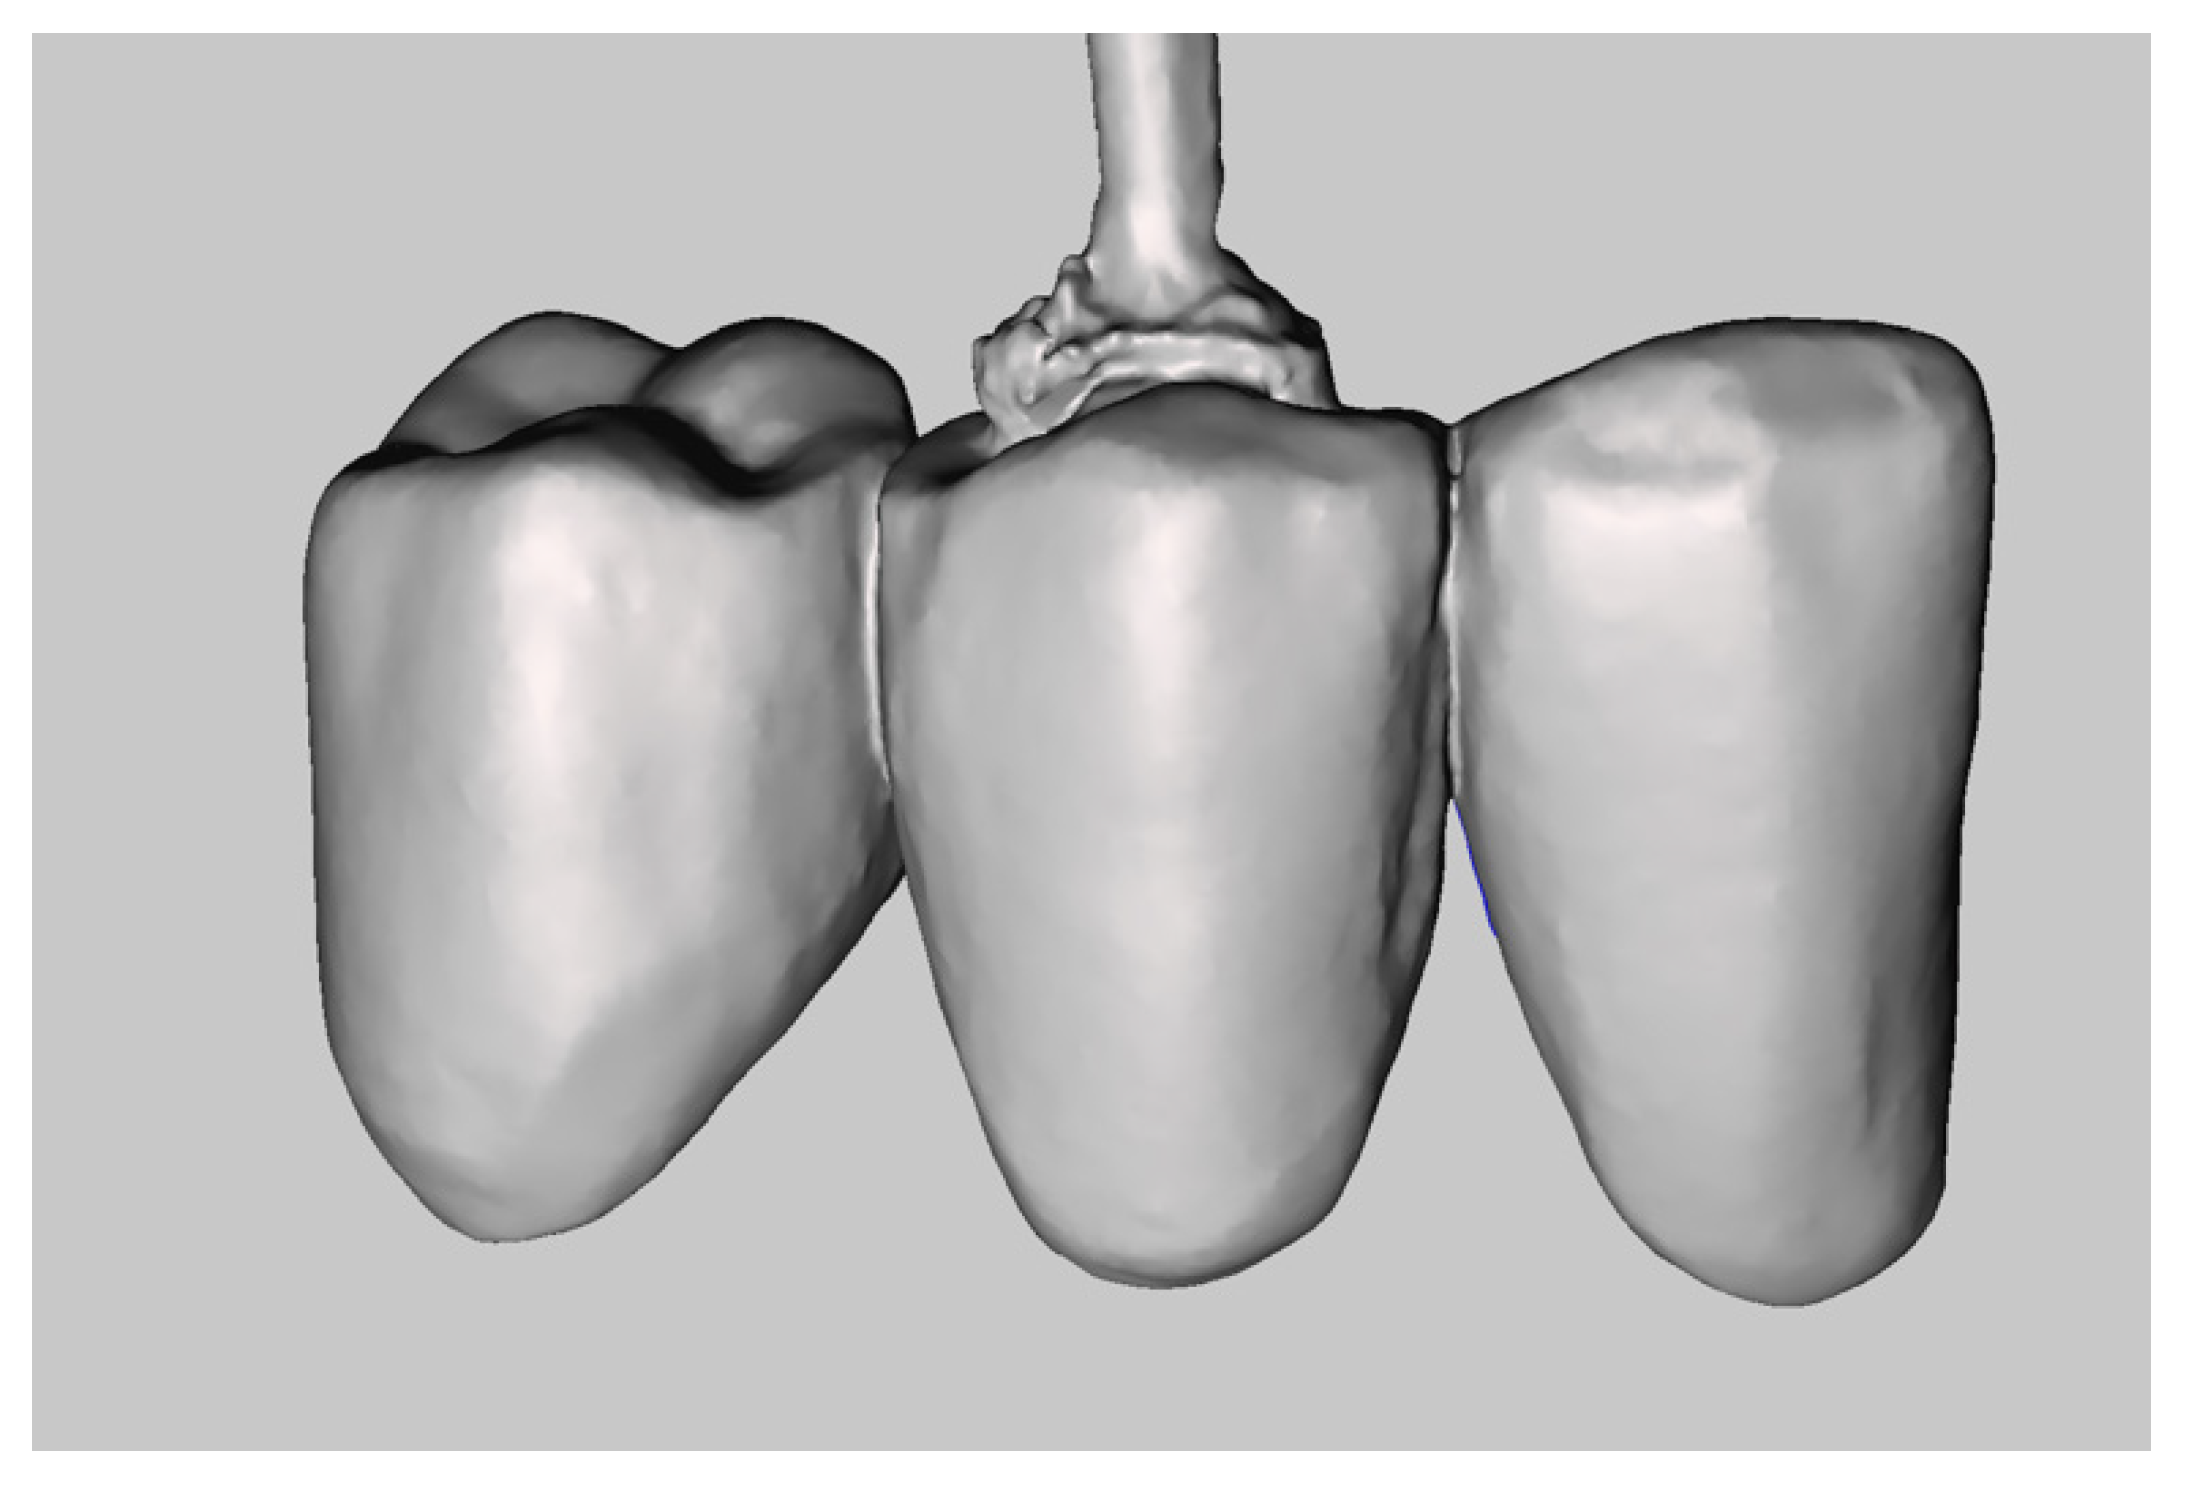

The master model was obtained by integrating two intraoral digital impressions (Figure 4), plus a scan of the temporary crowns using a Carestream CS3600 (Carestream Dental, Atlanta, GA, USA). The first impression scans the abutments, without retractor cords, following the recommended scanning protocol (both arches plus intercuspidal position). Next, an impression with the provisional restoration in place was taken. Subsequently, temporary crowns were scanned extraorally, acquiring their inner and outer margins (Figure 5). The resulting STL files were processed to produce a digital master model in which the data of the finish line of the abutments and of the surrounding tissues were derived from the temporary crowns. The workflow was performed using MeshMixer (Autodesk, Mill Valley, CA, USA) and Exocad (Align Technology, San Jose, CA, USA) (Figure 6).

Figure 5.

Scan of the provisional restoration.